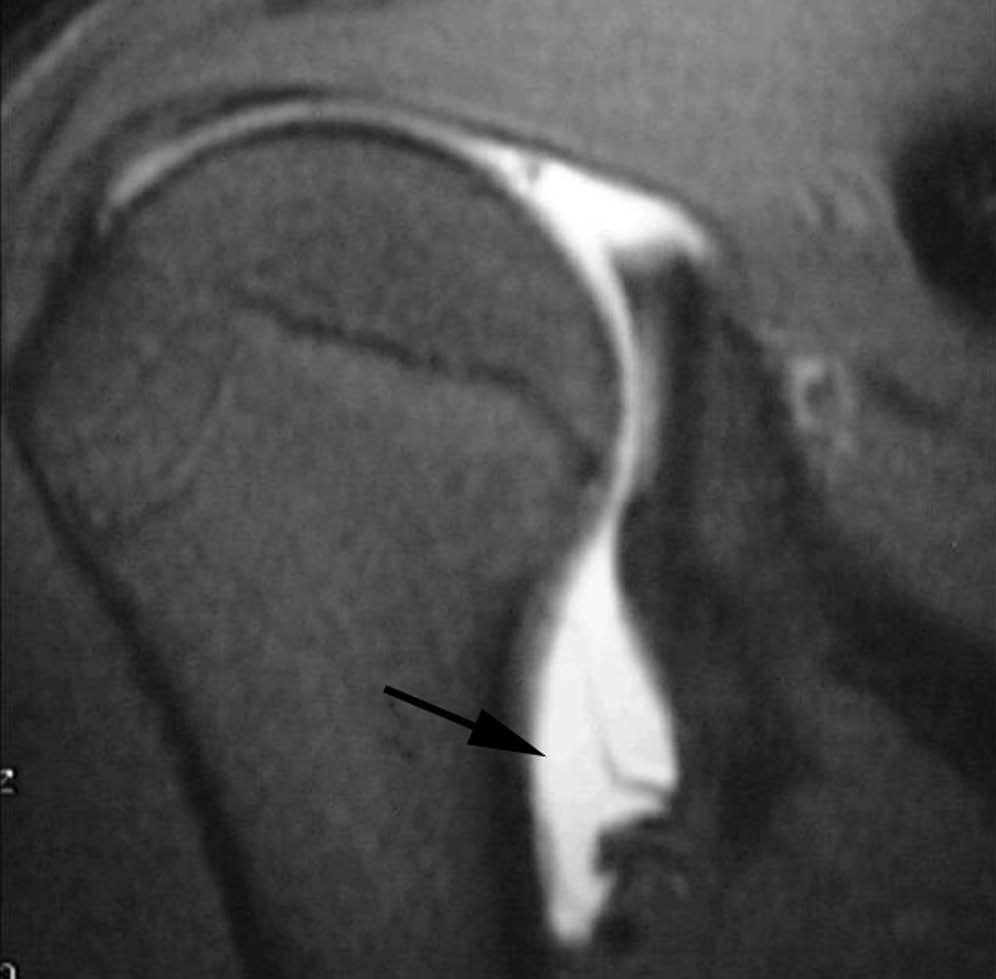

OCD (osteocondritis disecante)

La OCD es una fractura osteocondral común a muchas articulaciones, causada por fuerzas horizontales al plano articular. A diferencia de la lesión de GLAD, la OCD implica un fragmento óseo y de cartílago articular y generalmente se encuentra en el centro de la cavidad glenoidea, mientras que la lesión de GLAD ocurre en el borde de la misma (fig. 17).

Fig. 17.--OCD (osteocondritis disecante). Artrorresonancia indirecta coronal oblicua T1 con supresión grasa que revela una fractura osteocondral con el fragmento in situ (flechas). Nótese la presencia de contusión ósea del húmero debido a una fractura del trocánter.